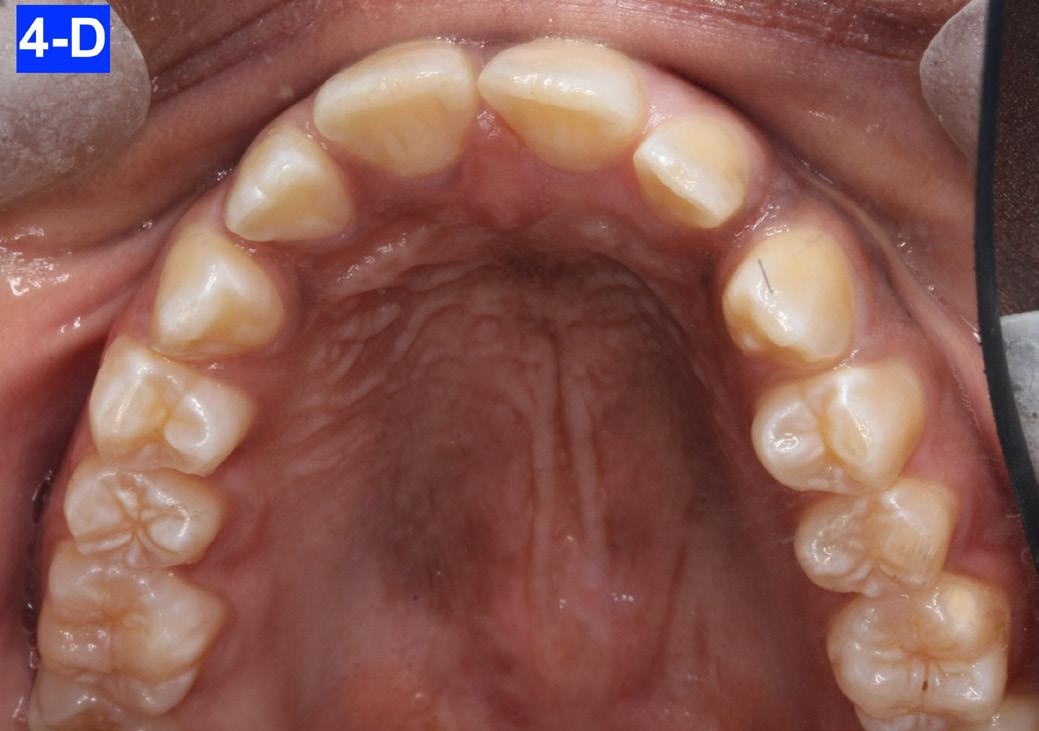

Clinical Micro-esthetic appraisal revealed a full Angle Class I molar and cuspid relationship. The arches were wide, there was generalized spacing in the anterior region. The patient had 2.0 mm overjet and -3.0 mm overbite. Maxillary lateral incisors appeared to be microdonts (Figures 4-A, B, C, D).

Fig. 4-D: Pre-treatment, MX occlusal view